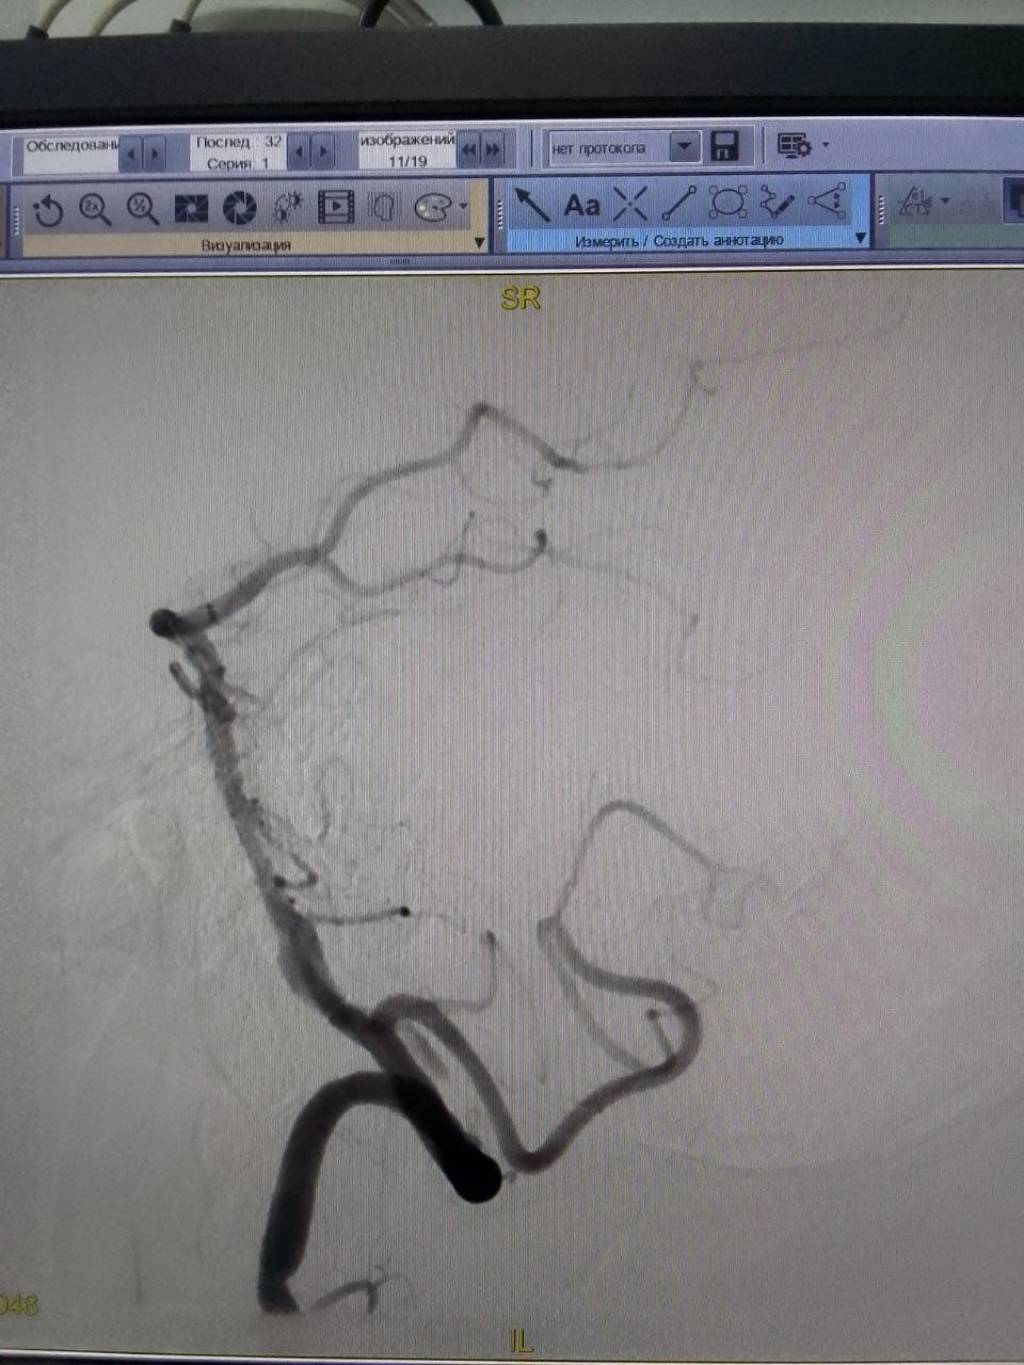

Bemorda zamonaviy angiografiya uskunalar orqali yuqori sifatli tasvirlar olinib, minimal invaziv yo‘l orqali bosh miya qon tomirlaridagi tromblar ochilib, uzoq muddatli davolashning oldi olindi. Hozirgi vaqtda bemorning ahvoli qoniqarli, u shifokorlar nazorati ostida davolanmoqda.